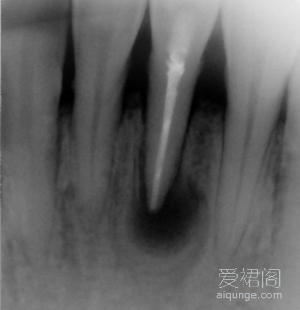

一个典型的根尖囊肿病例,对于这个患者来说,彻底的根管治疗是整个治疗过程的关键。首先,我们对这位患者进行了彻底完善的根管治疗,并要求患者在治疗过程中进行必要的抗炎治疗。患...